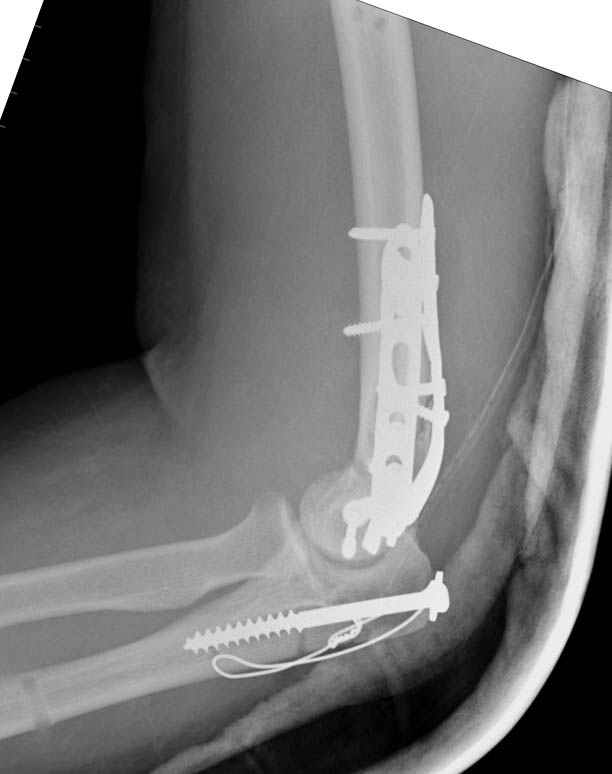

Солидарен с мнением обоих Александров (Челнокова и Рыкова): точную репозицию такого перелома вряд ли удастся выполнить закрыто. Даже во время открытого вмешательства это сделать непросто. Неслучайно предложен костно-пластический доступ с временным отсечением локтевого отростка. И по методу фиксации согласен с Александром Челноковым: 2 пластины. В качестве примера привожу рентгенограммы одного из наших пациентов с аналогичным повреждением.

С уважением, А. Золотов, Приморский край.

Примерный случай, только перелом был открытый, в задне-медиальной стороне рана около 2 см по характеру "изнутри кнаружи", неврологический статус со слабостью сгибания мизинца, также слабая абдукция и аддукция указательного пальца и сгибания в кисти.

Больному сделали обработку и наложили временный аппарат внешной фиксации плечо-предплечье.

На шестой день сделали открытую репозицию чрезлоктевым доступом двумя locking plate, локтевой нерв был ушибленным, после операции положительная динамика в Flexor Carpi Ulnaris. Фиксацию локтевого отростка произвели tension band technique с дополнительным шурупом.

Этапы операции на снимках....